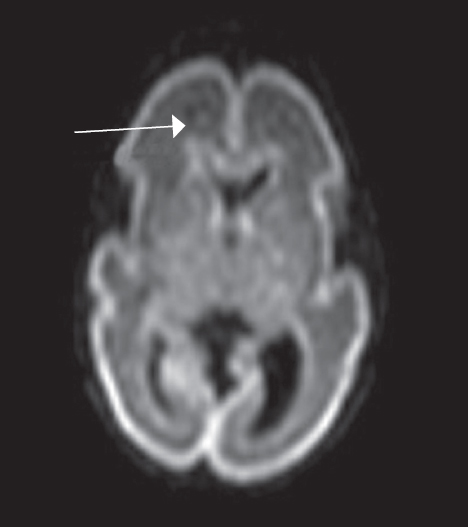

In MRI studies on premature infants at PCAs of 27–32 weeks, the germinal matrix was visualized in eight premature infants as DWI–MRI signals along the side walls of the brain lateral ventricles, as well as along the anterior horns above the caudate nuclei on both sides (Fig. 4). The germinal matrix was reliably detected in T2-weighted images from seven neonates (Fig. 5) and in T1-weighted images from two neonates (Fig. 6). The germinal matrix could not be visualized using FLAIR sequences.

Fig. 4. MRI of preterm newborn (PCA 28 wks.), DWI, axial plane. Hyperintensive MR-signal from the germinal matrix in the projection of the external parts of lateral ventricles (marked by arrows)

Рис. 4. МРТ головного мозга недоношенного ребенка (ПКВ 28 недель), ДВИ, аксиальная проекция. Визуализируется гиперинтенсивный МР-сигнал от герминального матрикса в проекции наружных отделов боковых желудочков (отмечен стрелками)

Using DWI–MRI, the sub-ependymal germinal matrix was detected in an overwhelming number of premature infants at PCAs of 27–32 weeks, and in two premature infants at PCAs of 33–34 weeks. The germinal matrix could be visualized on the DWI-sequence as a local hyperintense signal in the region of the anterior fields of lateral ventricles and a hyperintense linear signal in the external edge of the lateral ventricles (partially following the contour of the external wall of the ventricle). The DWI sensitivity in visualizing the germinal matrix exceeds that of other MRI pulse sequences and provides a more complete visualization picture of sub-ependymal germinal matrix regression in the ventricular areas of the brain in premature infants.